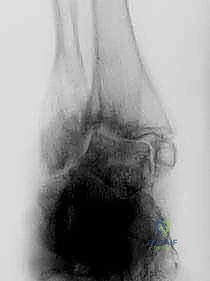

2. التصوير الطبي المتقدم

- الأشعة السينية (X-rays) أثناء الوقوف: وهي الخطوة الأهم لرؤية العظام تحت تأثير وزن الجسم. تظهر الأشعة اختفاء المسافة المفصلية، وتكوّن النتوءات العظمية، ودرجة التشوه المحوري.

- الأشعة المقطعية (CT Scan): ضرورية جداً لتقييم جودة العظام بشكل ثلاثي الأبعاد، وتحديد مدى التجاويف العظمية (Cysts) التي قد تحتاج إلى ترقيع عظمي أثناء الجراحة.

- التصوير بالرنين المغناطيسي (MRI): يُستخدم لتقييم الأربطة، الأوتار، وحالة النخر اللاوعائي في عظمة الكاحل.

في الحالات المرضية المتقدمة التي يستهدفها هذا المقال، يكون التلف قد طال كلا المفصلين. الألم لا يأتي فقط من حركة القدم لأعلى ولأسفل، بل أيضاً من أي محاولة للتكيف مع الأرض. الغضاريف التي كانت تعمل كوسائد ملساء قد اختفت تماماً، والعظام قد تشوهت، وتكونت نتوءات عظمية (Osteophytes) تزيد من تقييد الحركة وتضاعف الألم.

هذا هو المفصل الرئيسي الذي يربط بين عظام الساق (عظمة القصبة Tibia وعظمة الشظية Fibula) وعظمة الكاحل (Talus). وظيفة هذا المفصل الأساسية هي السماح للقدم بالحركة صعوداً (Dorsiflexion) وهبوطاً (Plantarflexion). عندما يتآكل الغضروف المبطن لهذا المفصل، تحتك العظام ببعضها البعض مع كل خطوة، مما يولد ألماً يشبه الطعن بالسكاكين.

يقع هذا المفصل مباشرة أسفل مفصل الكاحل، ويربط بين عظمة الكاحل (Talus) وعظمة العقب أو الكعب (Calcaneus). وظيفته تختلف تماماً؛ فهو المسؤول عن حركة القدم للداخل (Inversion) والخارج (Eversion). هذه الحركة هي التي تسمح لك بالمشي على الأسطح غير المستوية، مثل الحصى أو العشب، دون أن تفقد توازنك.